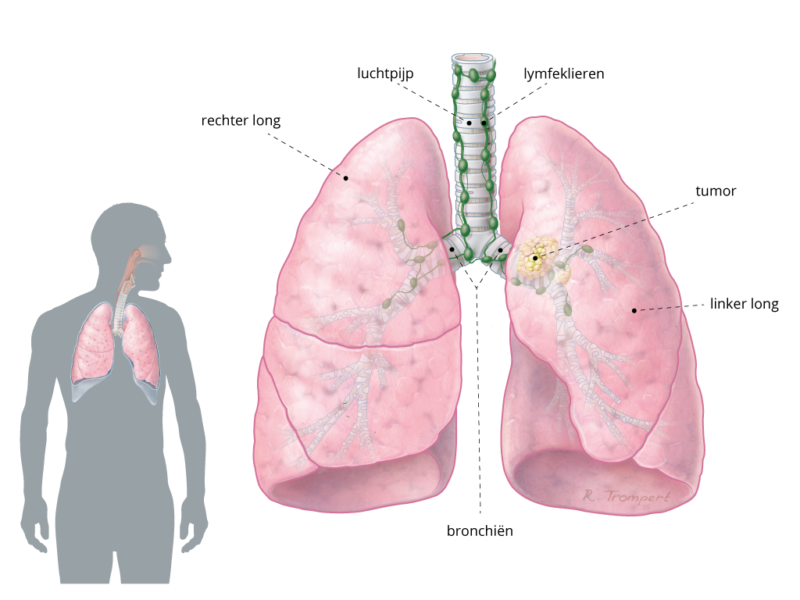

De longen Kanker.nl

De Koning liet zien dat twee factoren goed kunnen voorspellen of een vlekje op een long een kwaadaardige tumor wordt: de omvang en het tempo van de groei. Als het vlekje niet groter is dan 200.

Longkanker, symptomen en onderzoeken Pfizer

Longen En Luchtwegen

Bij een eerste onderzoek krijgt de arts een beeld van de algemene gezondheidstoestand van de patiënt. Hij vraagt naar symptomen en mogelijke risicofactoren (anamnese). Tegelijkertijd krijgt hij de eerste indicaties van verdenking op longkanker, bijvoorbeeld als de lymfeklieren op een typische plek opgezwollen zijn. Röntgenfoto's van de longen

Longfoto bij longkanker. Een longfoto is vaak het eerste onderzoek dat je krijgt als je klachten hebt die kunnen komen door longkanker. Met een longfoto kan de arts afwijkingen in de longen zien. Een afwijking hoeft niet meteen kanker te zijn. Als op de longfoto een afwijking te zien is, krijg je vaak ook een CT-scan.

Longkanker Oncozon

Er is een afwijking gezien op uw longfoto of van één van uw naasten. Mogelijk is het longkanker. Als u hiermee te maken krijgt is dit heel ingrijpend. U wilt zo snel mogelijk zekerheid en de beste behandeling. Het Centrum voor Longkanker biedt een rustige en vertrouwde omgeving. Bijna alle gesprekken met de verschillende zorgverleners vinden.

De meest voorkomende symptomen bij longkanker zijn: Een hardnekkige prikkelhoest, die langer dan 9 weken aanhoudt. Bloed in het opgehoeste slijm (zonder dat er een aanleiding voor is. Als je bijvoorbeeld steeds je keel schraapt en je keel geïrriteerd raakt, kan er een daardoor een beetje bloed in je slijm zitten).